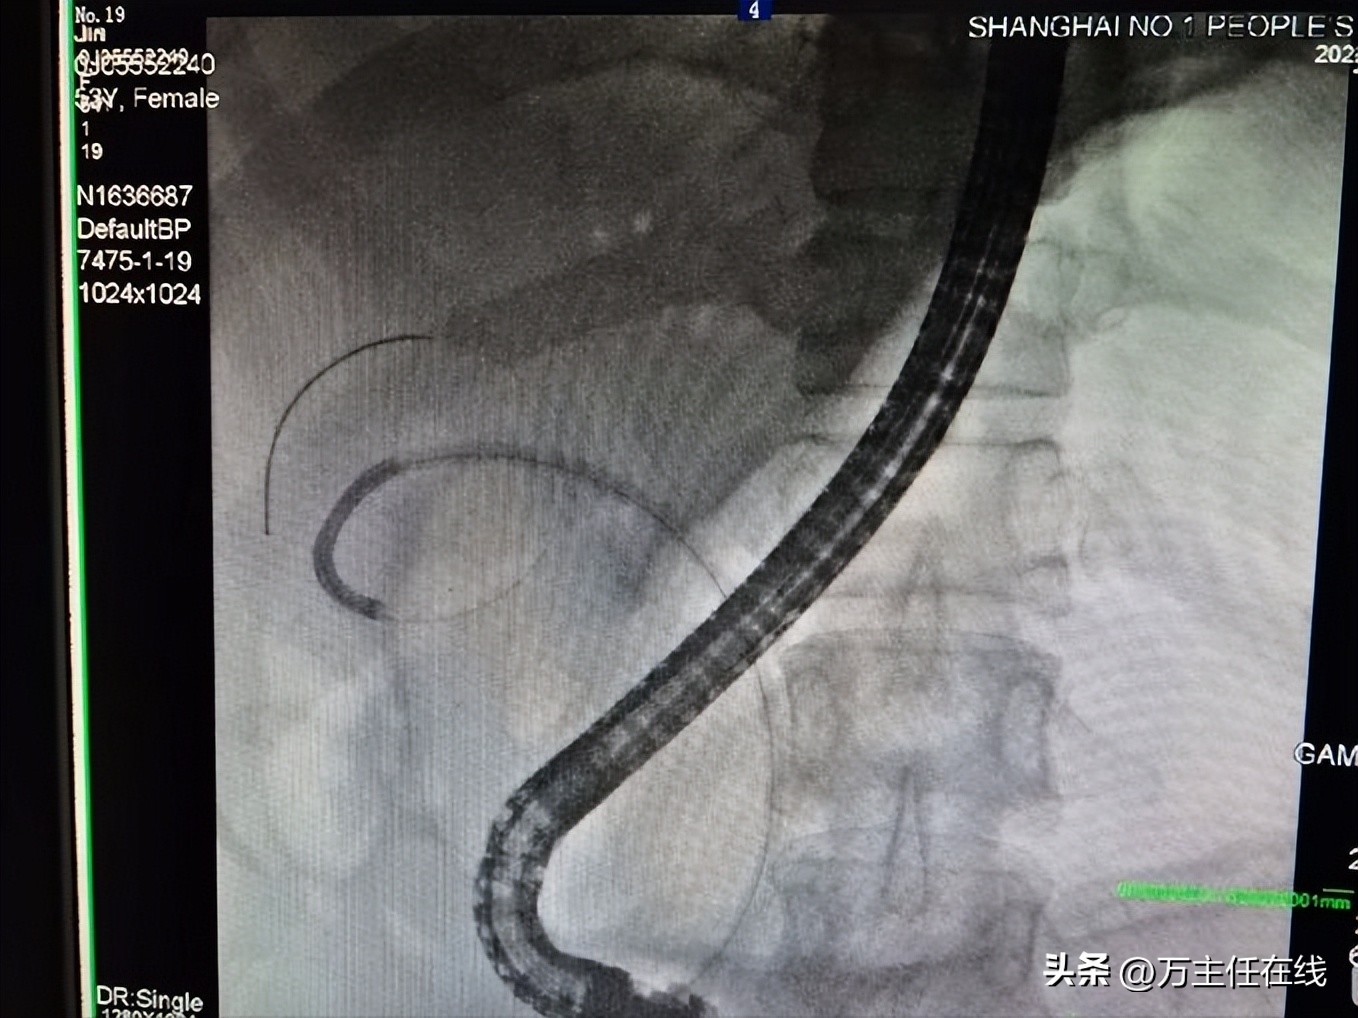

胆管、胰管及胆囊管支架置入后

胆道取石清理后,予胆管、胰管及胆囊管支架引流